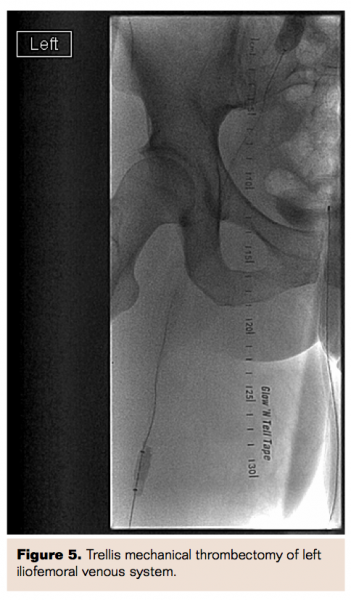

Initial imaging with lower extremity Doppler revealed a large, occlusive DVT extending from the left tibial vein to the left common iliac vein. There was also evidence of D-IVC on the initial Doppler imaging study. A computed tomography (CT) scan confirmed D-IVC and a filling defect in the left common iliac vein and no pulmonary embolism. Screening for thrombophilia revealed a heterozygous mutation for factor V Leiden. She was started on anticoagulation therapy with intravenous heparin but continued to have significant pain and swelling of the leg with preservation of arterial pulses.

Three weeks later, she was brought back to the cardiac catheterization laboratory for venography and for possible removal of the IVC filters. Venography revealed re-occlusion of the left iliac system secondary to thrombus. A decision was made to proceed with balloon angioplasty of the left iliac system. After multiple balloon dilatations, intravascular ultrasound (IVUS) was performed, which revealed compression of the left iliac vein by the right iliac artery. Two self-expanding 12 mm x 60 mm and 10 mm x 60 mm Protégé GPS self-expanding stents (Covidien Inc) were then deployed into the left common iliac venous system. There was excellent flow through the stents via both wide-open bilateral IVC and pelvic connectors. We chose not to remove the IVC filters at this juncture because of the presence of extensive clot burden. The pelvic connector between left IVC and right iliac vein was noted to be behind the aortoiliac bifurcation and was compressed. IVUS of the pelvic connector was performed, which confirmed the suspicion of compression. After performing balloon dilatation of the compression, a 12 mm x 40 mm Protégé GPS self-expanding stent was deployed which subsequently showed excellent flow in the connector and in bilateral IVC.